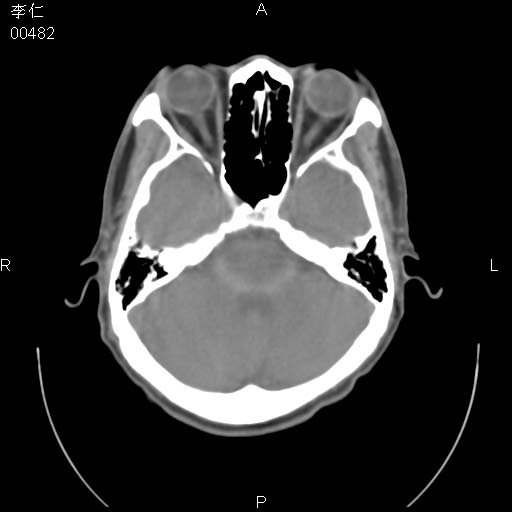

患者男,45岁。于二月前发现左眼稍肿,去看眼科,查肾功(—),来查ct,我看到的是左侧上眼睑内低密度影,ct值是-600到-700hu。

是一个副鼻窦的正常变异,脂肪瘤的密度不可能这么低,-600到-700.

只是空气而已,属正常ct表现。

正常表现,眼睑与结膜zhi间的空气

正常,为结膜囊内气体。

左侧眼球壁光滑,未见异常密度灶,眶内结构清晰,眼内肌、视神经均正常。所见低密度灶,本人考虑:1、五官科翻上睑造成;2、炎症(产气细菌感染)。